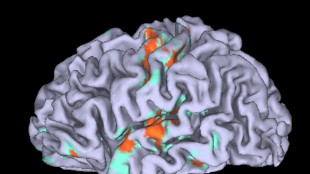

Cervello, individuati i neuroni che scatenano l'ansia

Una ricerca sui topi indica una nuova via per regolarli

Cervello, scoperta la regione dove si accende la fede calcistica

Modello per studiare anche fanatismo religioso e politico

Gli ormoni influenzano l'apprendimento, ricostruito il circuito

Esperimenti sui topi collegano gli estrogeni alla dopamina